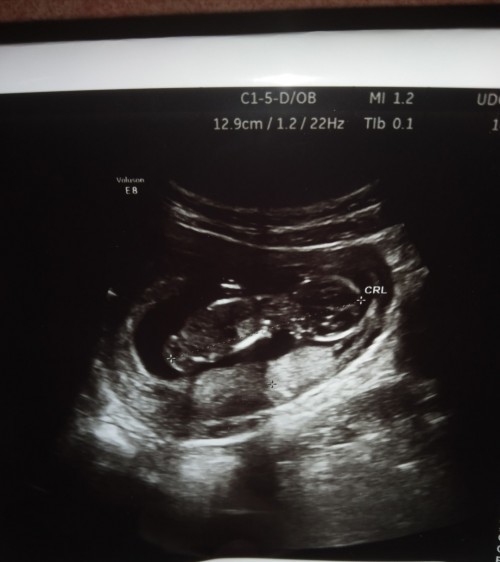

คลอด 29 มกราคมจ้า 16w